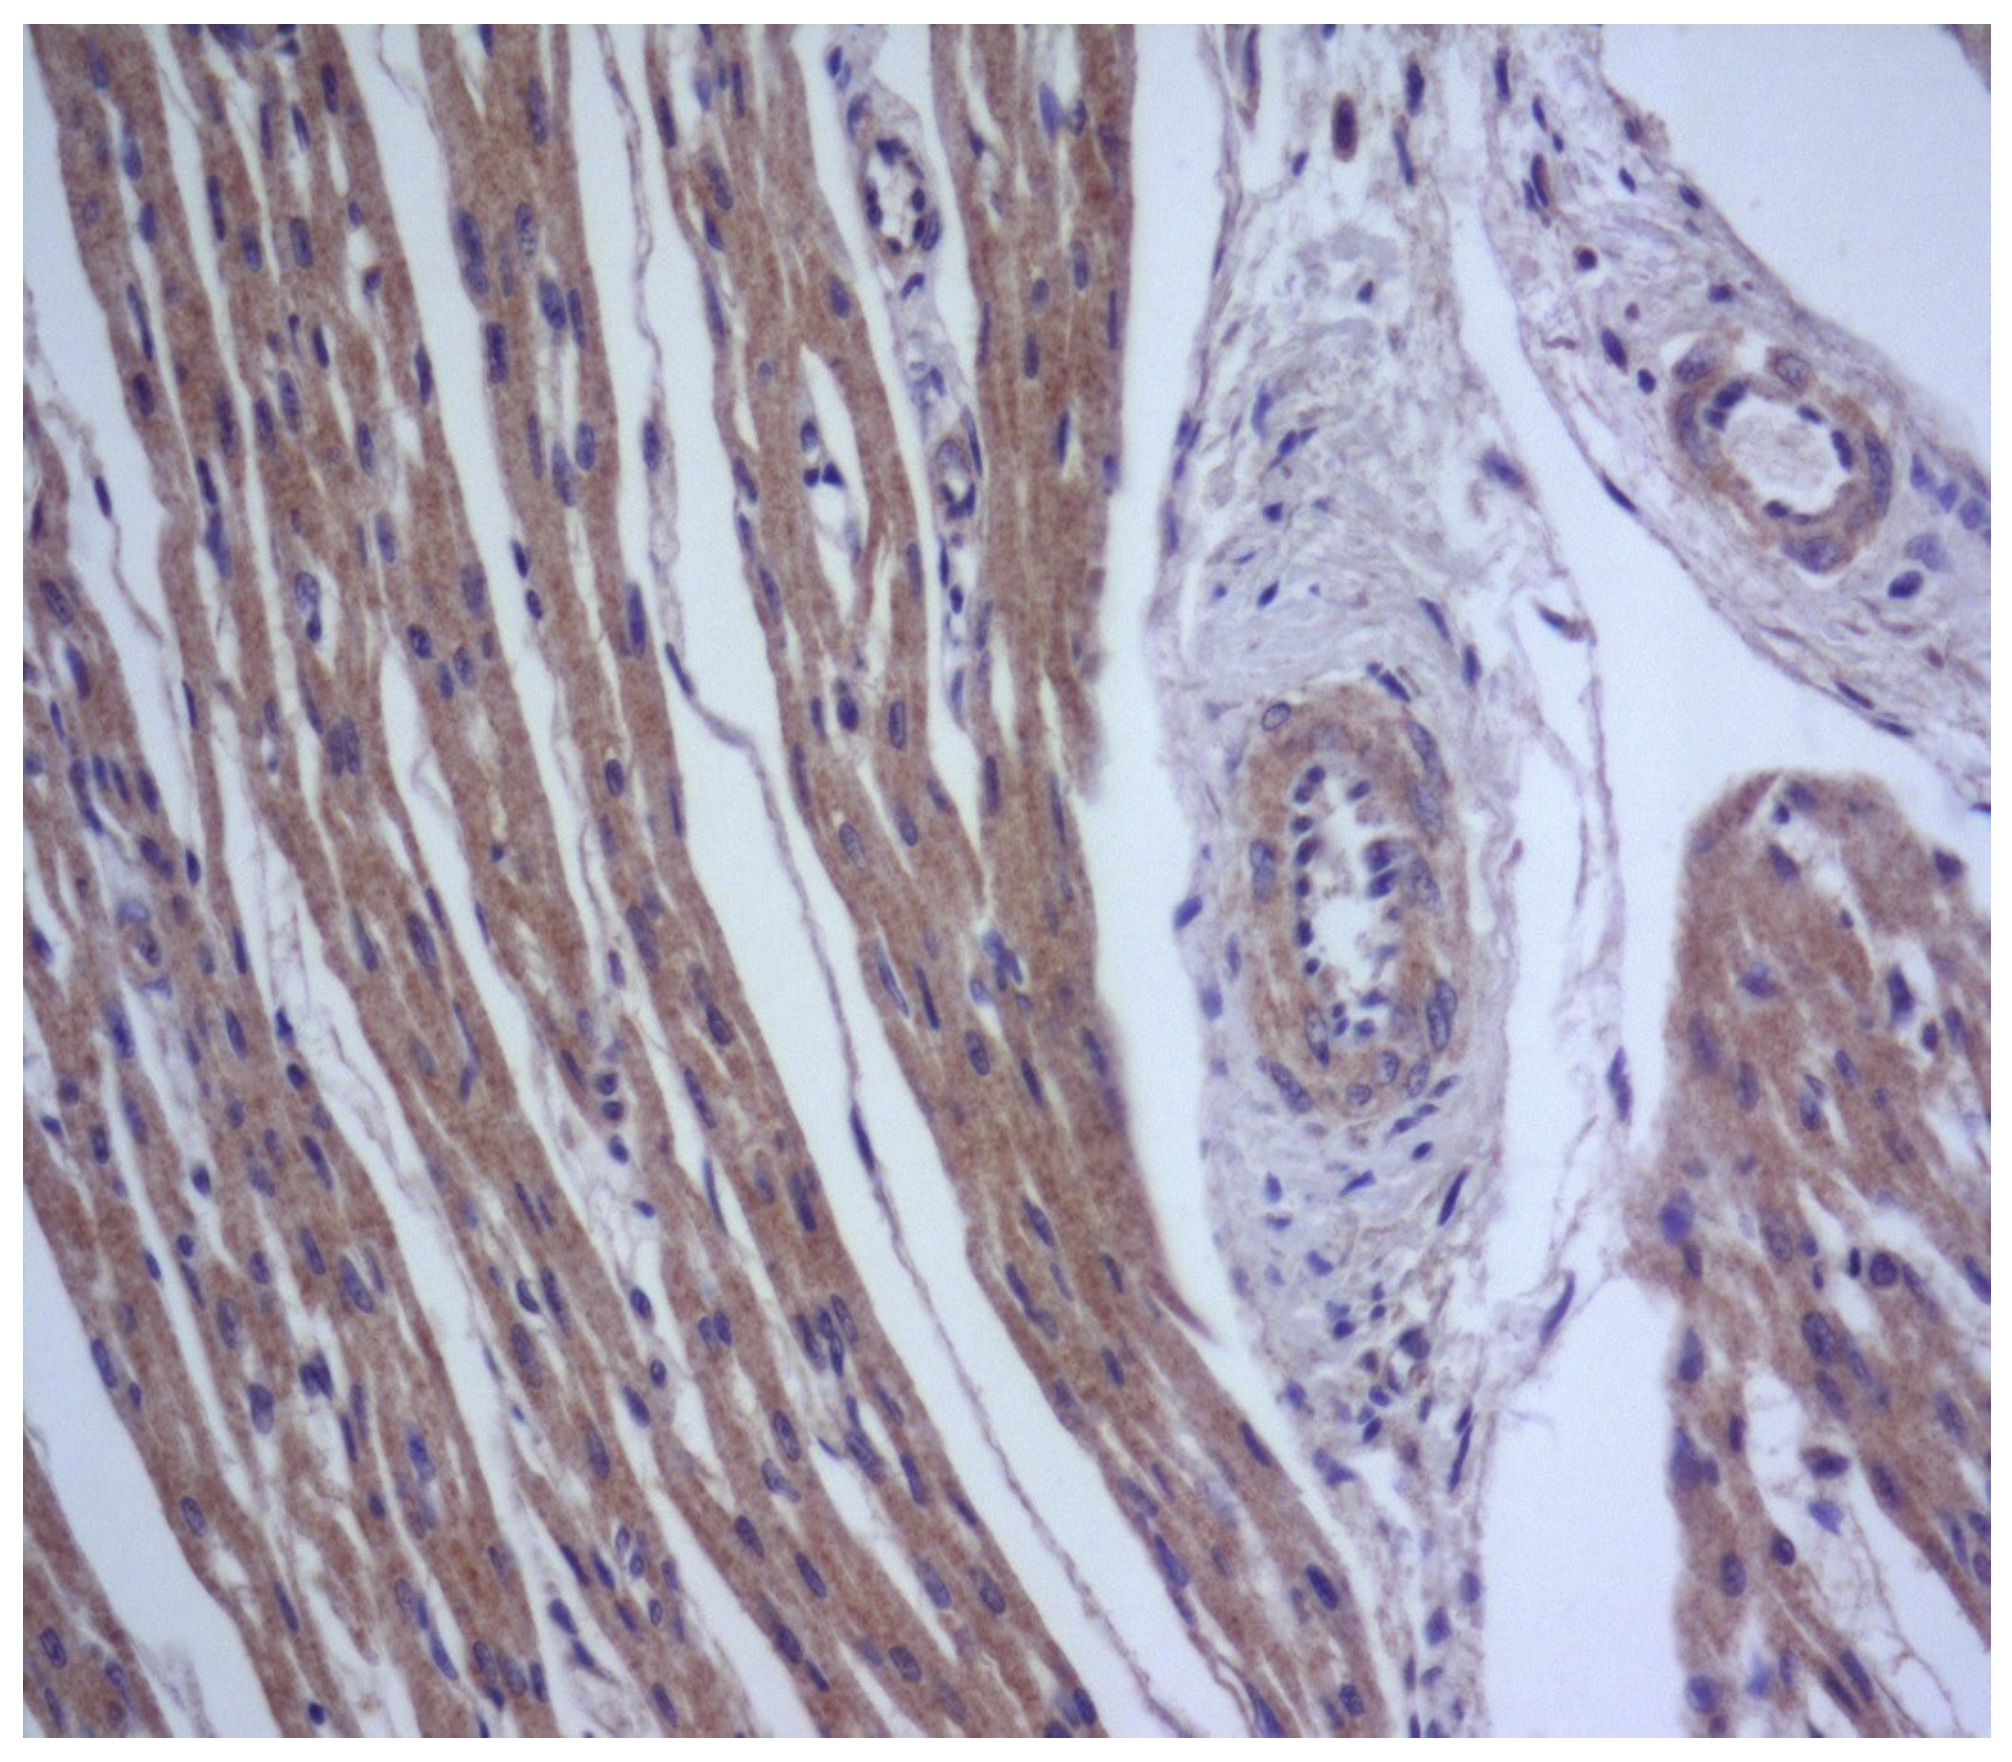

In parenchymal and non-parenchymal cells, herpes simplex virus antigens are expressed in the nuclei and/or cytoplasm. Similar to other herpes family viruses, cytomegalovirus displays a prominent pantropic behavior; however, cytomegalovirus-related damage to cardiomyocytes followed by relevant giant cell transformation occurs rarely, usually due to severe immunodeficiency [45]. Most often, cytomegalovirus-triggered heart lesions are limited to virus-induced alterations in the vascular endothelium (Figure 3) and parietal and valvular endocardium, as well as expression of virus-specific antigens observed in interstitial inflammatory infiltration and endothelial cells [46].

Figure 3. Expression of cytomegalovirus antigens (brown staining) in transformed endothelial cells during generalized intrauterine cytomegalovirus infection. IHH, mouse monoclonal anti-CMV-specific staining (DAKO, Santa Clara, CA, USA), DAB. SW. ×400.